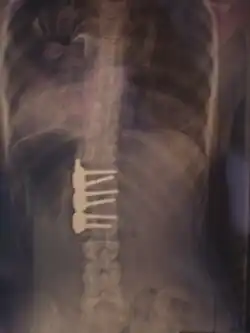

Operacja z dostępu tylnego

Podczas operacji z dostępu tylnego nacięcie jest robione wzdłuż pleców. Po nacięciu skóry i odsunięciu mięśni, umieszczane są implanty, aby zredukować skrzywienie i zapobiec ponownemu krzywieniu. Następnie kręgosłup jest okładany „wiórkami” kostnymi, pobranymi zwykle z biodra pacjenta. Po zrośnięciu się przeszczepionej tkanki kostnej z kręgosłupem (co może trwać do 12 miesięcy), implanty przestają spełniać swoją funkcję i stają się zbędne. Zwykle nie ma jednak wskazań medycznych do usuwania ich[16].

- Niekiedy należy zastosować leczenie operacyjne. Podstawowymi wskazaniami do leczenia operacyjnego są: wartość kątowa skrzywienia powyżej 40° (według Cobba), progresja skrzywień, względy kosmetyczne, ból[8].